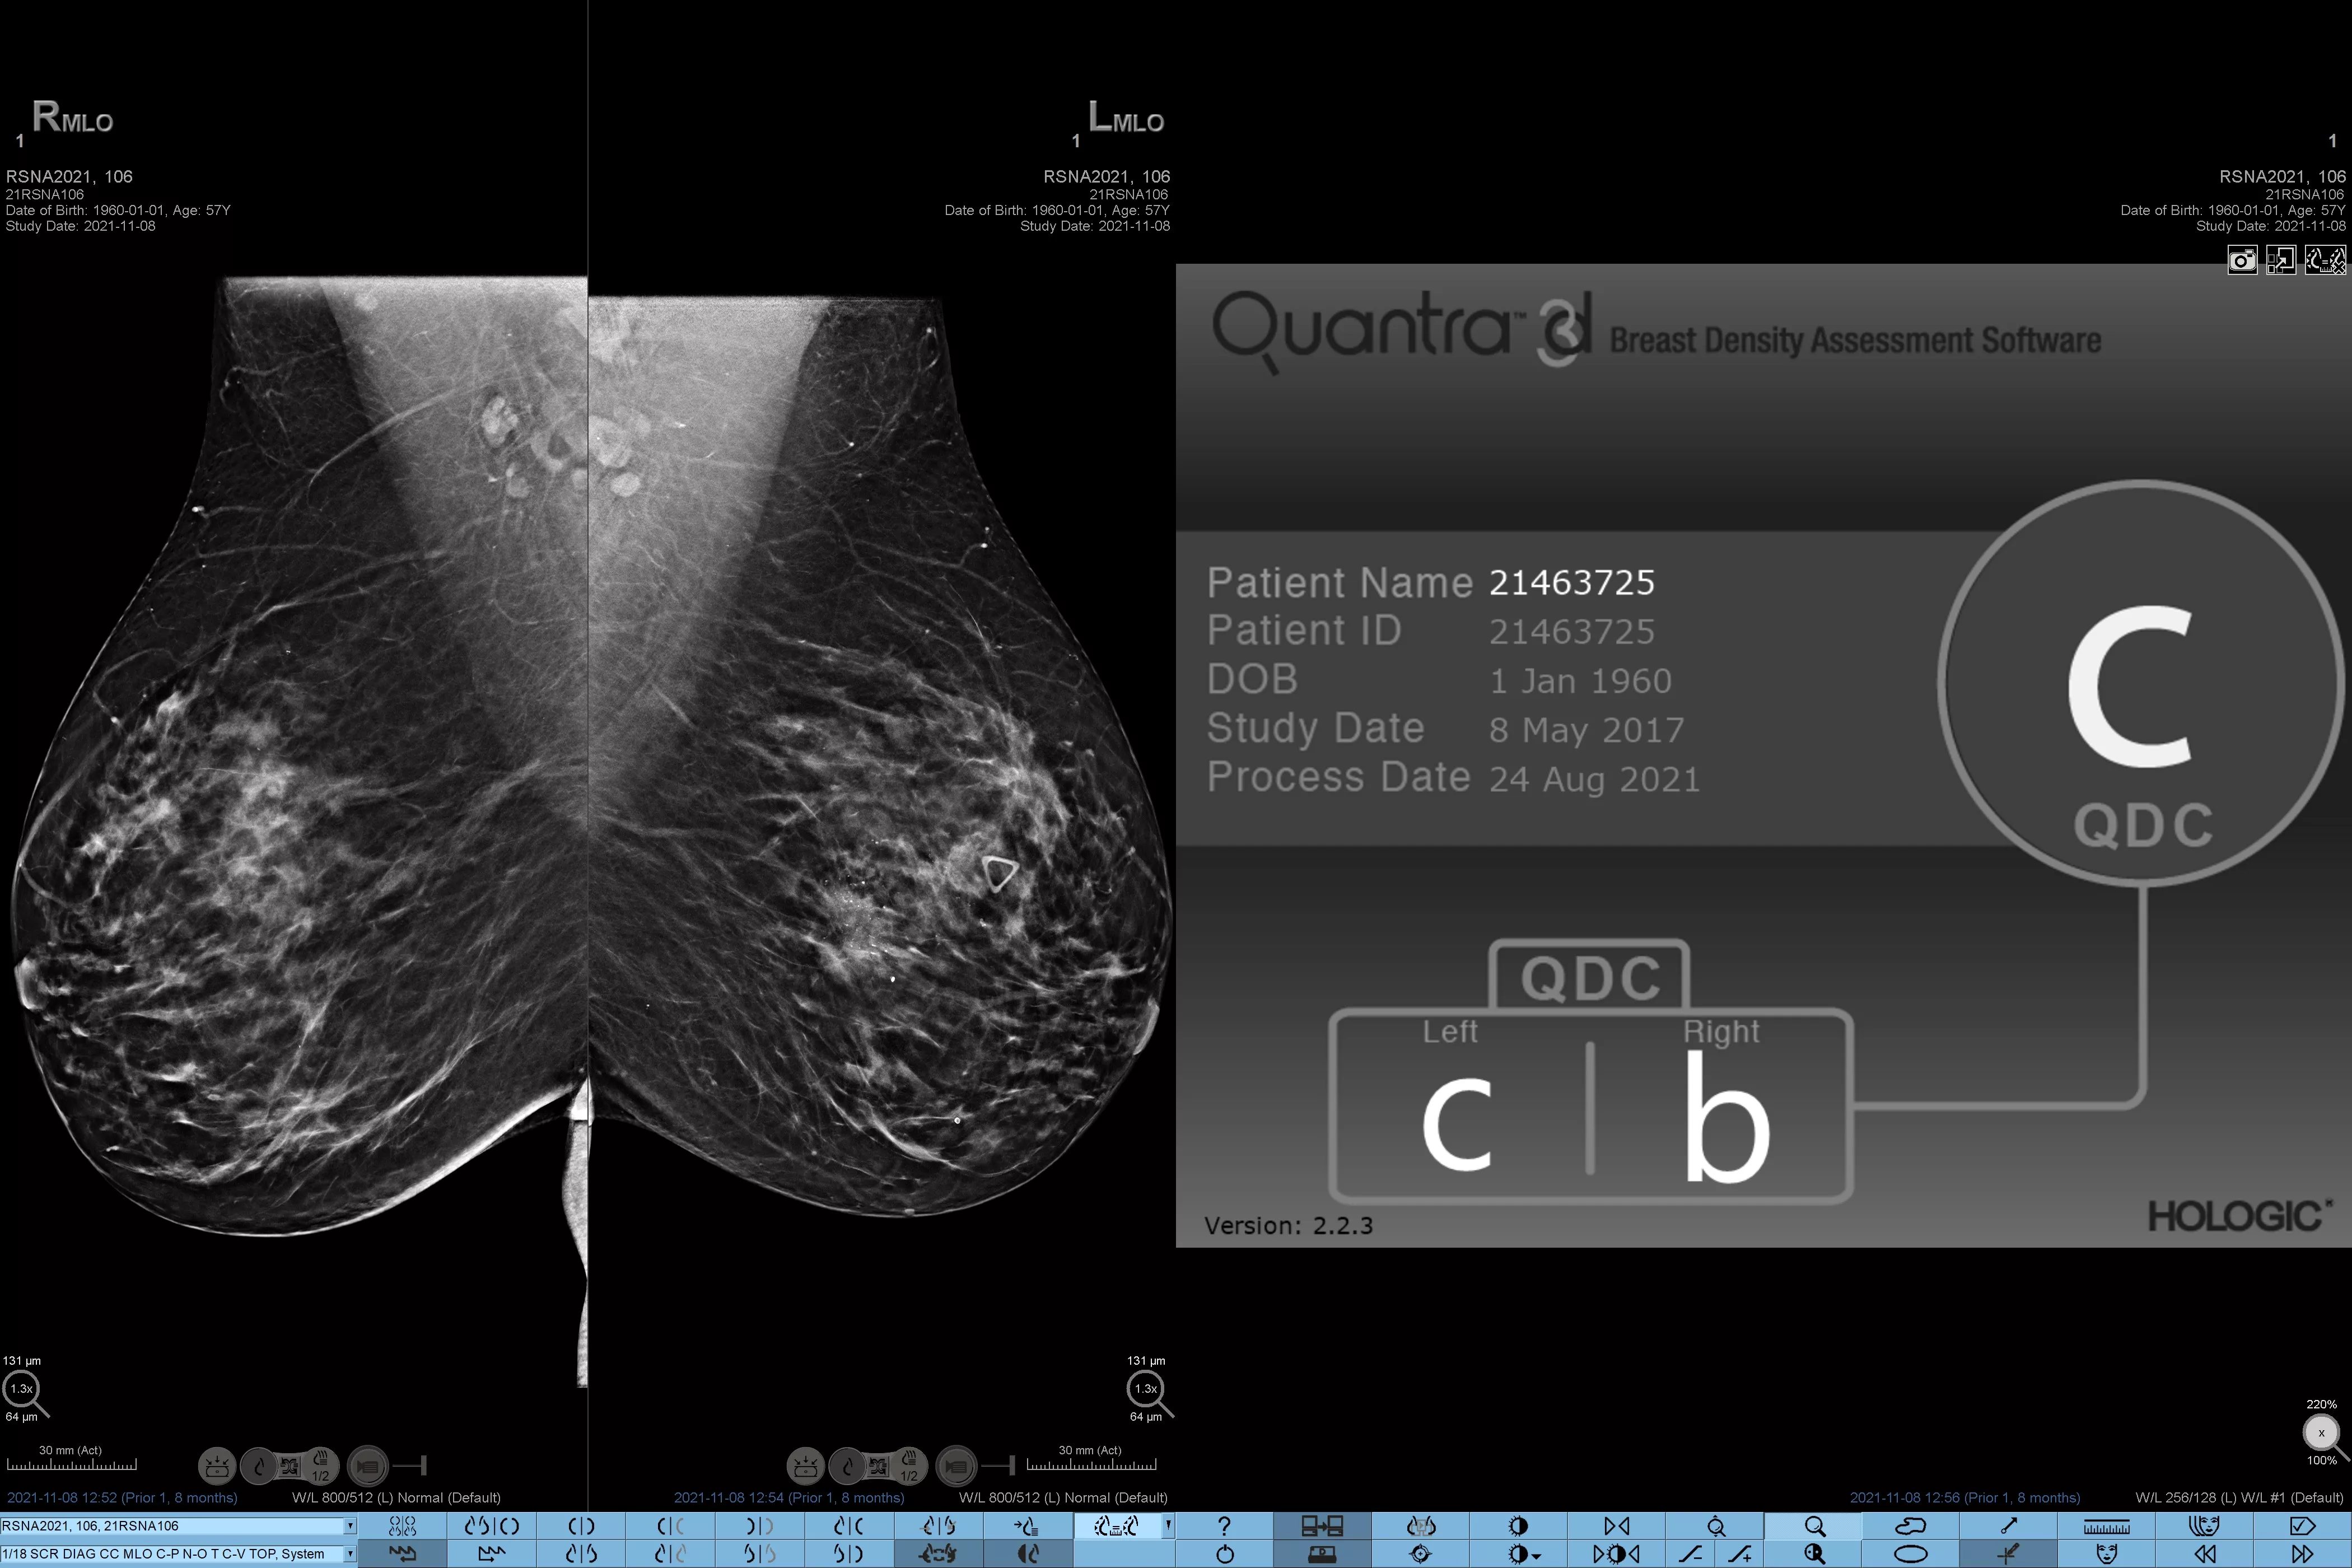

Higher breast density is known to increase a woman’s risk for breast cancer.1 The need for accurate, unbiased analysis is therefore critical. Powered by machine learning, Quantra technology software analyses both 2D™ and tomosynthesis images for distribution and texture of parenchymal tissue. It categorises breasts in four breast composition categories consistent with guidance from the American College of Radiology (ACR) BI-RADS Atlas 5th Edition.2

Quantra software’s unbiased algorithm analyse both 2D and tomosynthesis images to support your analysis by:

• Overcoming subjectivity in visual assessment, providing more consistent, and more reliable scoring.*

*Scores are based on ACR BI-RADS categories, in line with the revised guidance by the American College of Radiation (ACR) BI-RADS Atlas 5th Edition. This accounts for pattern and texture, compared with volume, when determining density.

8. Breast composition categories as described in ACR BI-RADS Atlas.